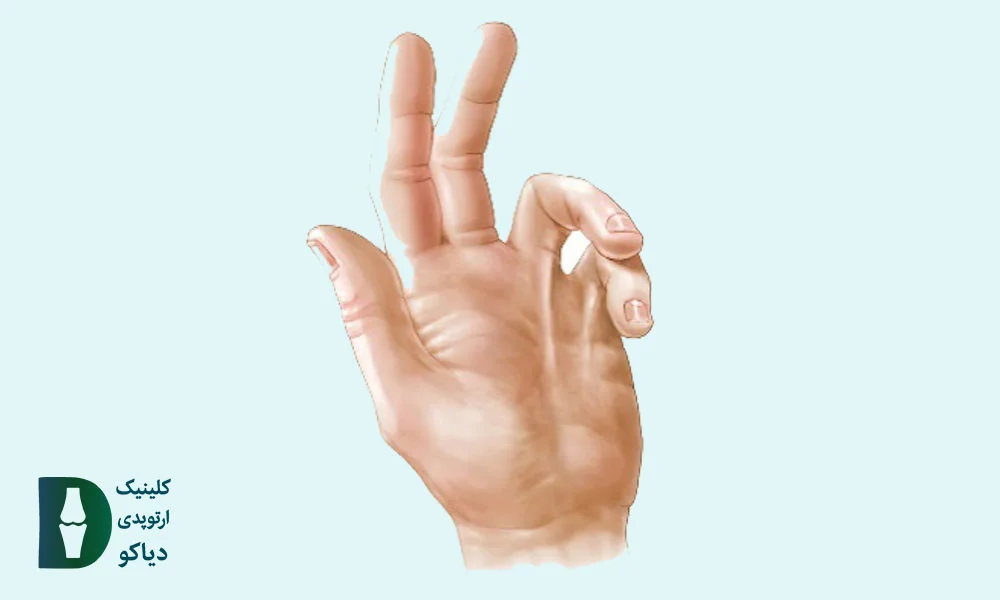

اگر هنگام باز و بستهکردن انگشتان، احساس قفلشدگی، صدای تق یا درد دارید، ممکن است دچار عارضهی انگشت ماشهای شده باشید. این وضعیت معمولاً در یک انگشت بروز میکند، اما اگر چند انگشت همزمان درگیر شوند، میتواند نشانهای از بیماریهای زمینهای مانند دیابت یا آرتریت روماتوئید باشد.

در اغلب موارد، انگشت شست، میانی یا حلقه بیشتر از سایر انگشتها دچار این مشکل میشوند. با این حال، برای تشخیص دقیق، انجام یک تست ساده در خانه میتواند مفید باشد.

![]() قفلشدگی دائم در وضعیت خمیده: احتمال وجود دفورمیتی یا گرید ۴ که نیازمند بررسی فوری پزشکی است.

قفلشدگی دائم در وضعیت خمیده: احتمال وجود دفورمیتی یا گرید ۴ که نیازمند بررسی فوری پزشکی است.

انگشت قفلشده است و بیمار قادر به خمکردن فعال آن نیست. |

انگشت در وضعیت خم باقی مانده و دچار محدودیت دائمی حرکت شده است. |

انگشت ماشهای در کودکان (بهویژه در شست) معمولاً بهصورت مادرزادی بروز میکند و برخلاف فرم اکتسابی در بزرگسالان، دردناک نیست، اما میتواند باعث گیرکردن دائمی انگشت در حالت خمیده شود. در این حالت، کودک قادر به صافکردن شست خود نیست، حتی با کمک دست دیگر و علت اصلی این مشکل، تشکیل یک گره کوچک (ندول) در تاندون خمکننده و تنگی غلاف اطراف آن است که مانع از حرکت روان تاندون میشود.